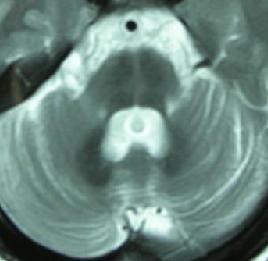

病理改變:顯微鏡下觀察可見脊髓前角細胞減少,伴膠質細胞增生,殘存的前角細胞萎縮大腦皮質的分層結構完整,錐體細胞減少伴膠質細胞增生。脊髓錐體束有脫髓鞘現象而運動皮質神經元細胞完好,表明最初的改變產生於神經軸突的遠端逐漸向上逆行累及大腦中央前回的錐體細胞此種改變又稱為逆行性死亡。一些生前僅有下運動神經元體徵的ALS患者死後屍檢可見顯著的皮質脊髓束脫髓鞘改變表明前角細胞功能受累嚴重掩蓋了上運動神經元損害的體徵。

還有一些臨床表現典型的ALS其病理改變類似於多系統變性,即有廣泛的脊髓結構損害脊髓前角錐體束脊髓小腦後束脊髓後索的神經根間區、Clarke核以及下丘腦、小腦齒狀核和紅核均有神經元細胞脫失和膠質細胞增生(Terao,1991)。

由於上位運動神經元變性,脊髓側索中的皮質脊髓束的軸索消失和萎縮,髓鞘染色其部位淺染。前角和腦神經運動核的下位運動神經元變性,其結果前根或運動神經的軸索消失、萎縮,變成白色。這些神經元支配的骨骼肌中,產生廣泛的神經源性的肌纖維萎縮。